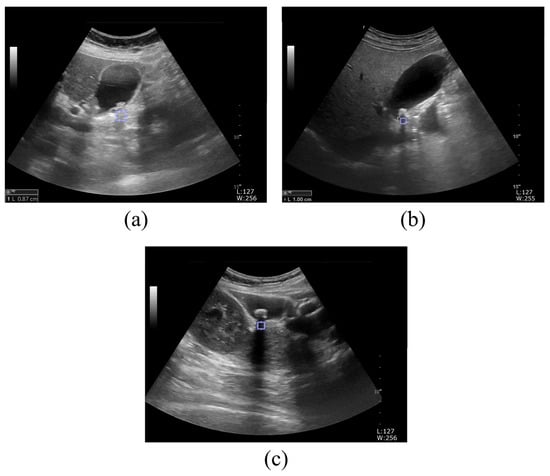

Quantitative Evaluation of Kidney and Gallbladder Stones by Texture Analysis Using Gray Level Co-Occurrence Matrix Based on Diagnostic Ultrasound Images

2.1. Ultrasound Image Acquisition